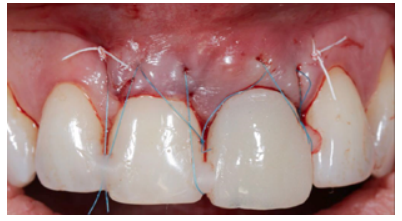

Due to a 2 mm gingival recession in the URCI, the CTG obtained was of sufficient size to encompass the region of this tooth and to be able to treat this recession simultaneously with the OII procedure. It was adapted to the recipient region with a 5.0 polytetrafluorethylene (PTFE) suture with mesial and distal fixation points, which guaranteed proper vascularisation of the graft (Figures 14A, 14B and 14C).

To complete the surgical approach, the provisional prosthesis was placed with the already made PE and 3 points of coronal traction were carried out, anchoring them to the contact points of the provisional and adjacent teeth with a 6.0 monofilament suture (Figure 16).